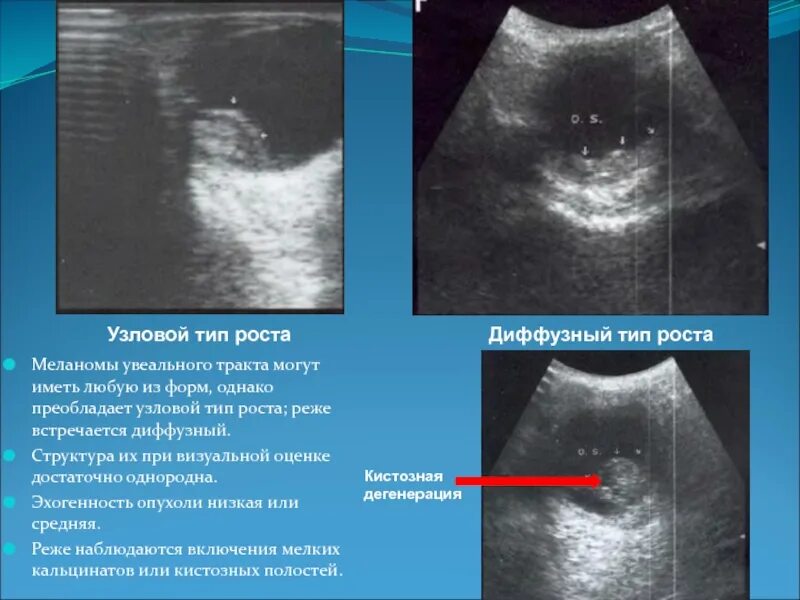

Повышенной эхогенности неоднородной структуры